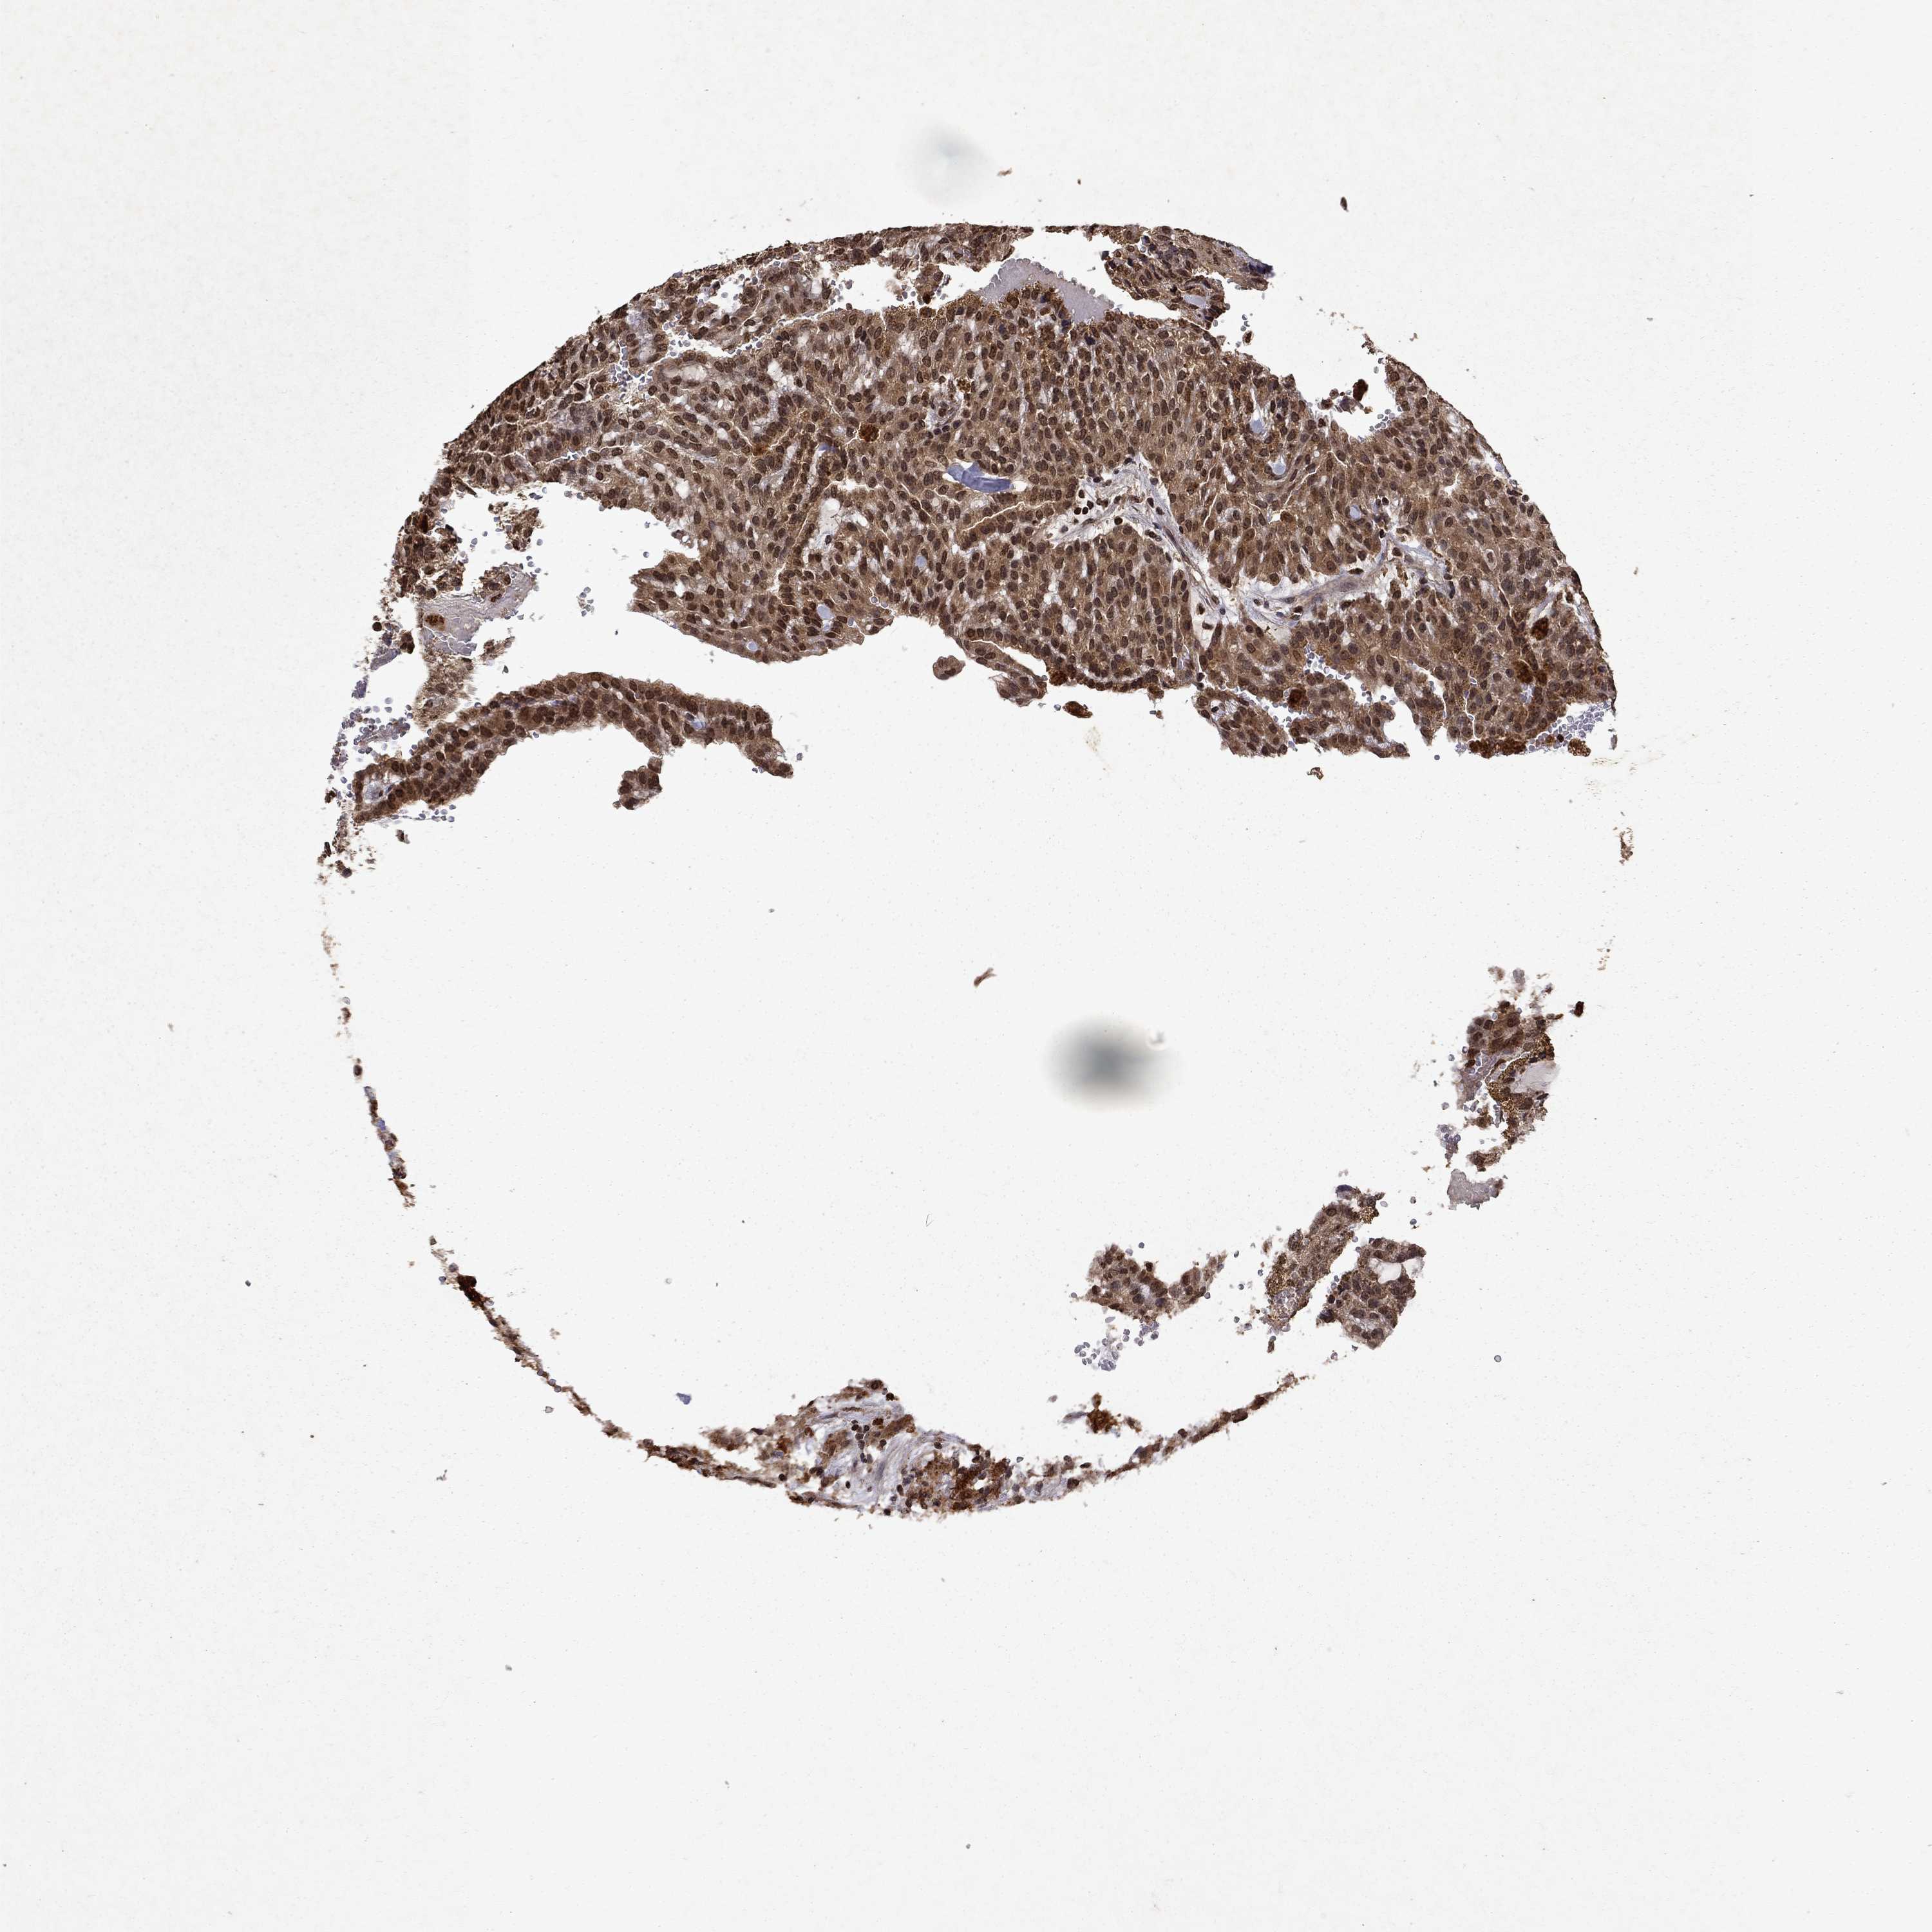

PIN4

KIDNEY RENAL CLEAR CELL CARCINOMA (TCGA) - Interactive survival scatter ploti

The Survival Scatter plot shows the clinical status (i.e. dead or alive) for all individuals in the patient cohort, based on the same data that underlies the corresponding Kaplan-Meier plots. Patients that are alive at last time for follow-up are shown in blue and patients who have died during the study are shown in red.

The x-axis shows the expression levels (FPKM) of the investigated gene in the tumor tissue at the time of diagnosis. The y-axis shows the follow-up time after diagnosis (years). Both axes are complimented with kernel density curves demonstrating the data density over the axes. The top density plot shows the expression levels (FPKM) distribution among dead (red) and alive patients (blue). The right density plot shows the data density of the survived years of dead patients with high and low expression levels respectively, stratified using the cutoff indicated by the vertical dashed line through the Survival Scatter plot. This cutoff is automatically defined based on the FPKM cutoff that minimizes the p-score. The cutoff can be changed by dragging the vertical line or by entering a cutoff value in the square labeled "Current cut-off".

Under the Survival Scatter plot the p-score landscape (black curve; left axis) is shown together with dead median separation (red curve; right axis). Dead median separation is the difference in median mRNA expression between patients who have died with high and low expression, respectively. It is calculated as follows: median FPKM expression of dead patients with high expression - median FPKM expression of dead patients with low expression. This is intended to aid the user in visually exploring custom cutoffs and the associated p-scores and dead median separation.

Individual patient data is displayed and can be filtered by clicking on one or more of the category buttons on the top of the page. Categories describing expression level and patient information include: high, low, alive, dead, female, male and tumor stages. The scale of the x-axis can be toggled between linear and log-scale by clicking on the "x log" button. Mouse-over function shows TCGA ID, patient information and mRNA expression (FPKM) for each patient.

& Survival analysisi

Kaplan-Meier plots summarize results from analysis of correlation between mRNA expression level and patient survival. Patients were divided based on level of expression into one of the two groups "low" (under cut off) or "high" (over cut off). X-axis shows time for survival (years) and y-axis shows the probability of survival, where 1.0 corresponds to 100 percent.

PIN4 is not prognostic in Kidney Renal Clear Cell Carcinoma (TCGA)

Best expression cut offi

Based on the FPKM value of each gene, patients were classified into two groups and association between prognosis (survival) and gene expression (FPKM) was examined. The best expression cut-off refers the FPKM value that yields maximal difference with regard to survival between the two groups at the lowest log-rank P-value. Best expression cut-off was selected based on survival analysis .

When clicking on this number, the vertical dashed line indicating cut-off, the interactive survival plot, and the Kaplan-Meier curve will be adjusted to show results based on the best expression cut-off.

: 17.75

TCGA RNA samplesi

RNA-seq data is reported as average FPKM (number Fragments Per Kilobase of exon per Million reads), generated by the The Cancer Genome Atlas (TCGA) .

Normal distribution across the dataset is visualized with box plots, shown as median and 25th and 75th percentiles. Points are displayed as outliers if they are above or below 1.5 times the interquartile range. FPKM values of the individual samples are presented next to the box plot.

Average pTPM 21.9

Number of samples 521